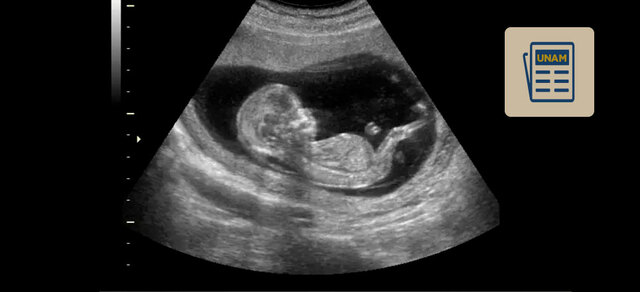

Se invento el ultrasonido, hasta entonces es utilizado para el diagnóstico de embarazo u otras patologías en los órganos.